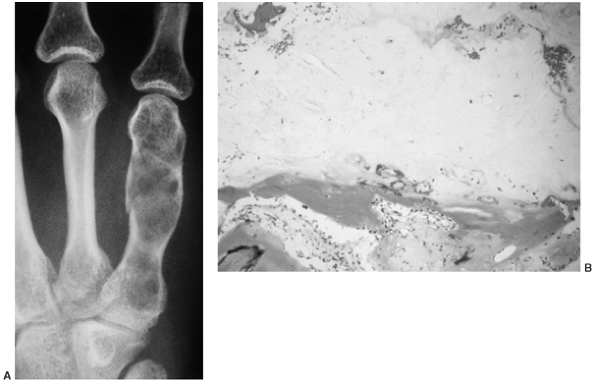

![]() |

Figure 14.6 A:

Typical histologic appearance of an osteoid osteoma. There is immature (woven) bone lined with osteoblast. Between the woven bone is a vessel-rich fibrous stroma. There is no atypia, and the few mitotic figures are normal (10 × magnification). B: Higher magnification (40 ×) of the histology of the osteoid osteoma shown inA. The woven bone lined with osteoblast is easily seen. The red blood cells indicate the intense vascularity that is typical of this lesion. |